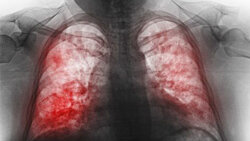

Двухсторонняя пневмония - что это

Пневмония объединяет в себе ряд заболеваний, каждое из которых имеет своих возбудителей и способ лечения. Возбудителями пневмонии, как правило, являются бактерии, грибки и вирусы. А самым надежным методом лечения антибиотики. По форме пневмония подразделяется на одностороннюю и двухстороннюю. При односторонней пневмонии поражено одно лёгкое, а при двухсторонней – сразу два. Двухсторонняя пневмония может развиться на фоне брохита. А вот причиной односторонней могут стать бактерии (стафилококк, пневмококк, гемофильная палочка и вирусные инфекции)...